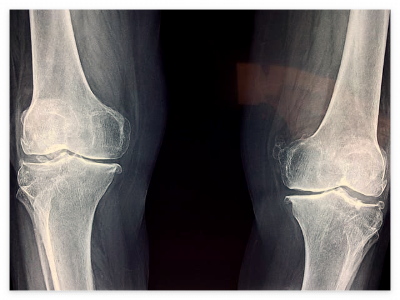

1. 무릎 인공관절 수술이란?

퇴행성 관절염, 류마티스 관절염 등으로 무릎 연골이 닳아 통증과 운동 제한이 심할 때 시행하는 수술입니다.

2. 건강보험 적용 기준

✅ 건강보험 적용 대상

- 만 60세 이상

- 만 60세 미만이라도 의학적 필요성이 있는 경우 (중증 관절염, 심한 통증, 일상생활 장애 등)